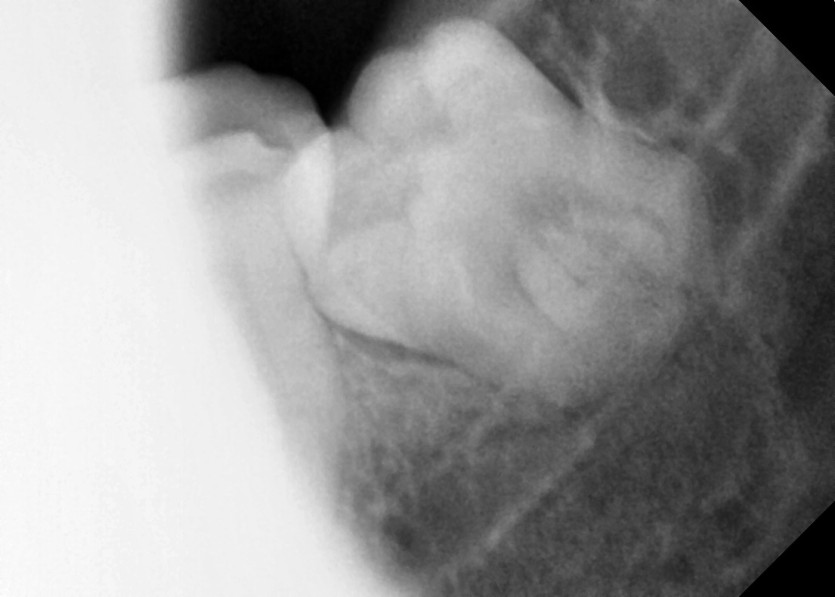

#18,28,38,48 사랑니 발치

구강 외과 전문의가 당일 발치했습니다.